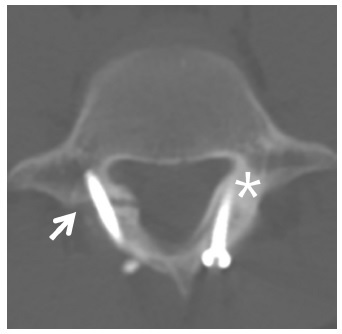

研究的观察指标包括:VAS 疼痛评分、ODI 功能评分和 SF-12 健康量表评分。其中 SF-12 健康量表评分包括物理评分和精神评分两个部分。影像学上的观察指标包括:峡部裂缺口间距和融合率。峡部不愈合定义为 CT 上融合骨块不连续(图 2 和图 3)。

图 3 术后 1 年的 CT 提示峡部不愈合